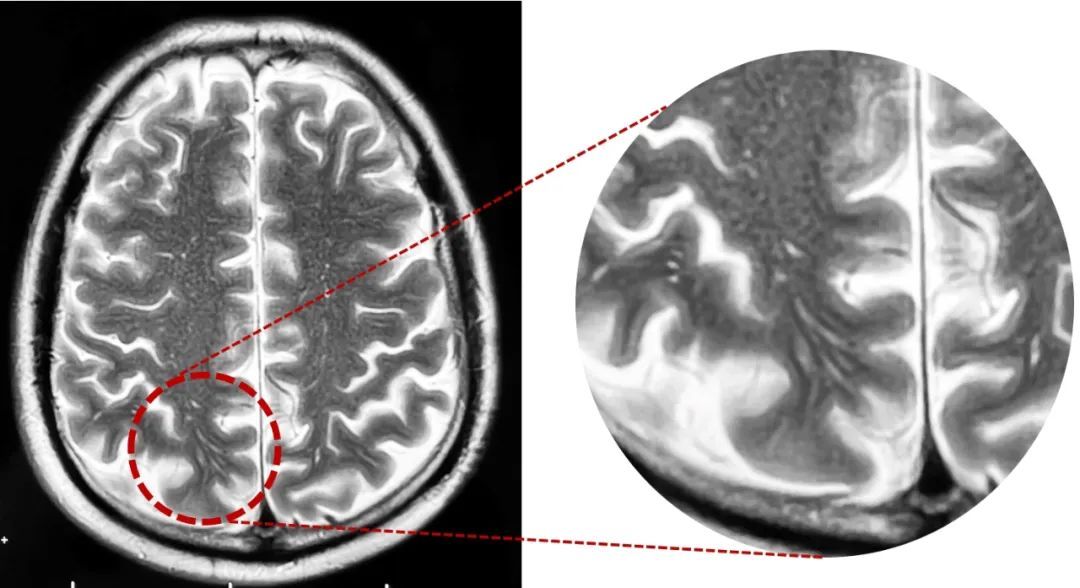

一名31岁的男性,无意中核磁共振发现如下的影像:

答案:这是相对比较罕见的扩大的血管周围间隙。

因为血管周围间隙内填充有组织液,因此其在CT和MRI上的影像学表现与脑脊液完全一致。CT为低信号;T1低信号、T2高信号、FLAIR低信号、DWI等信号。当成像平行于血管时,血管周围间隙表现为线性,垂直于血管时呈圆形或椭圆形,直径一般小于3mm。

54岁男性,因急性脑梗死入院,意外发现脑内蜂窝状的扩大的血管周围间隙。